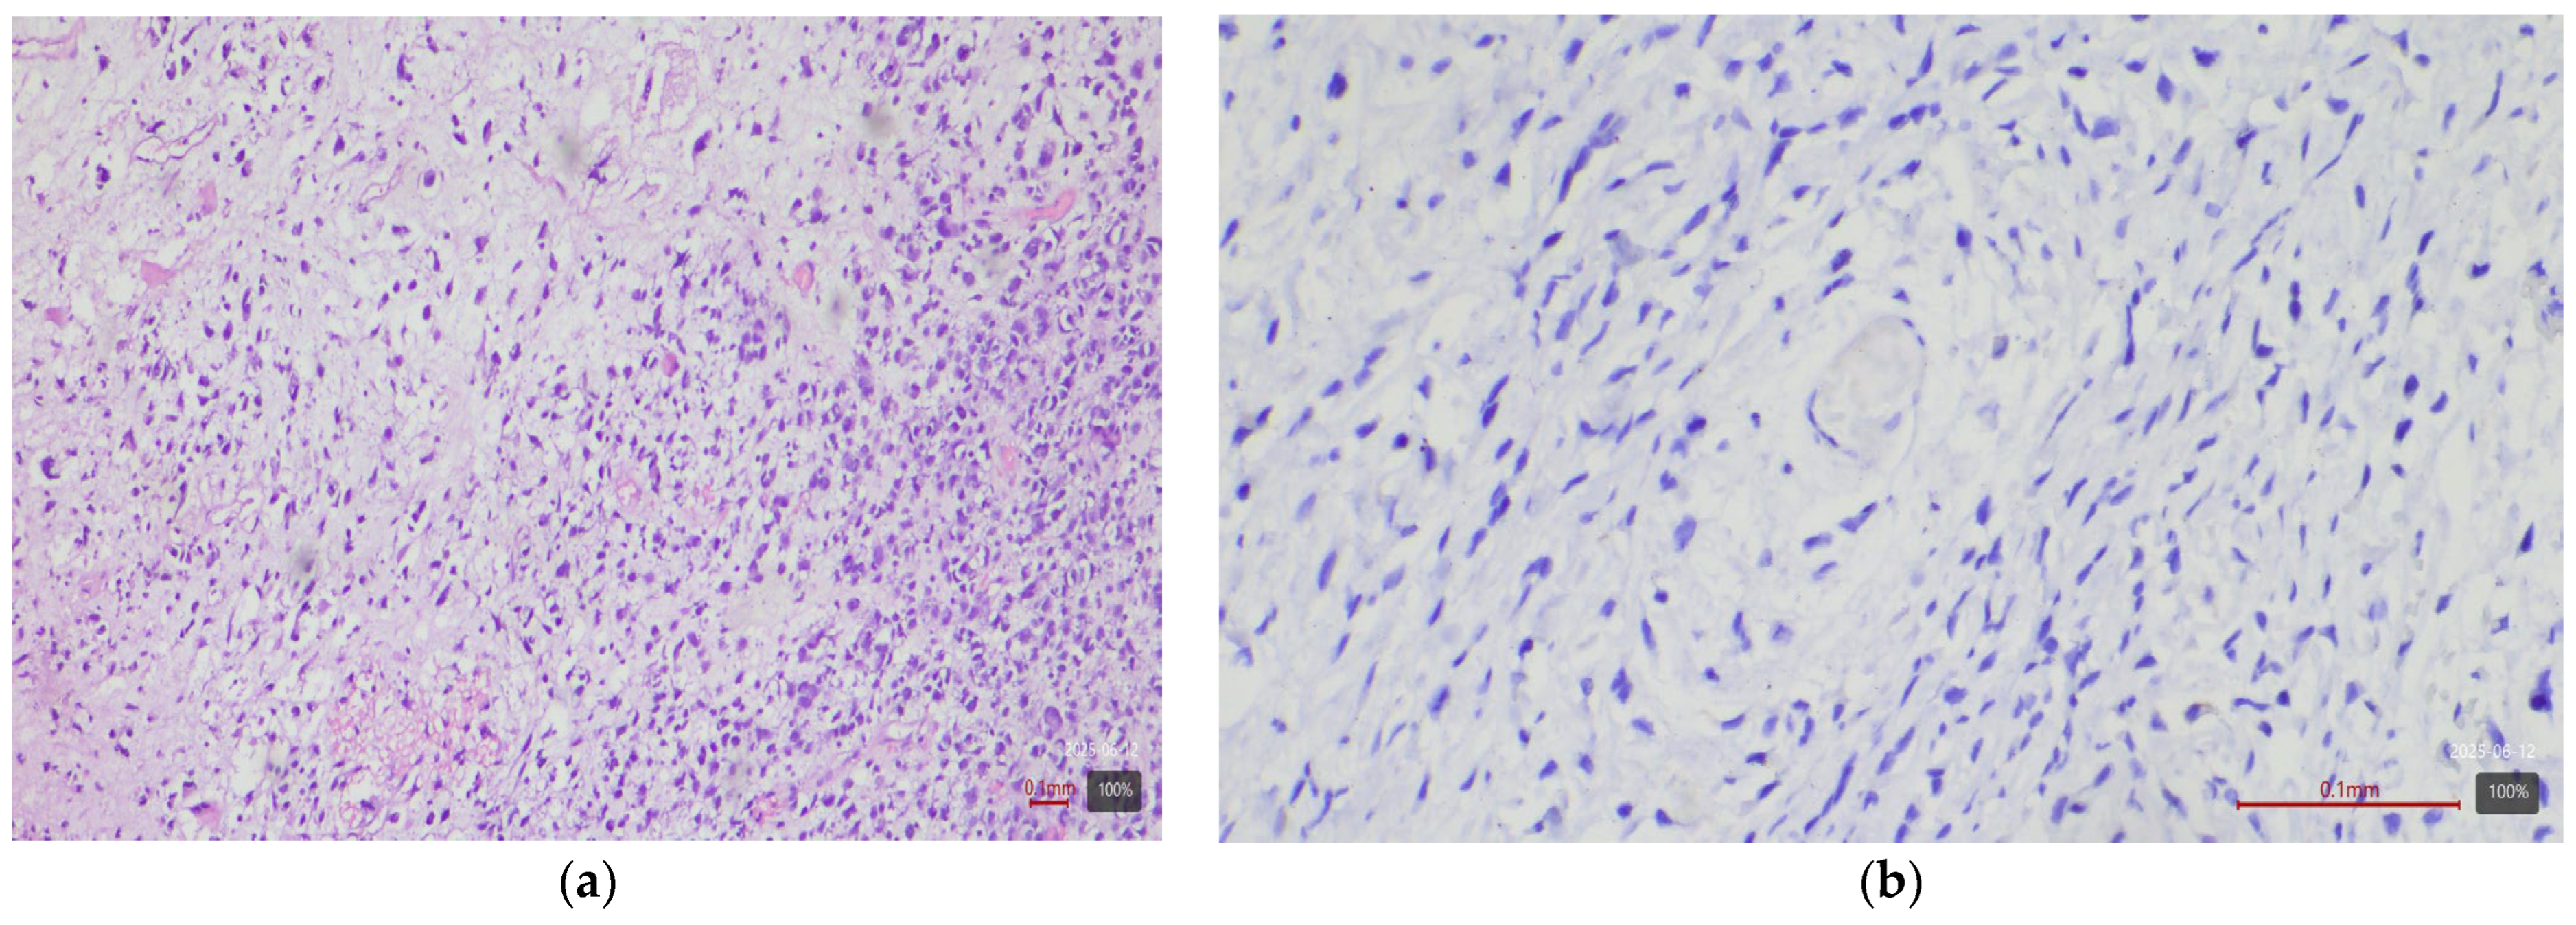

2.3. Histological and Molecular Subtyping of Tumors

2.4. Immunohistochemical Study of HER2

2.5. Interpretation of HER2 Status